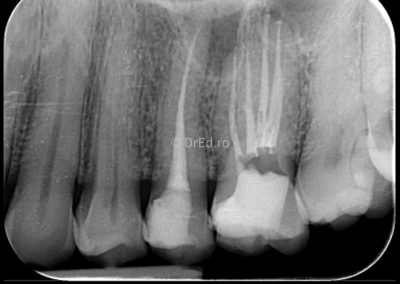

Galerie

Toate imaginile, fotografiile și radiografiile publicate pe acest site sunt protejate prin drepturi de autor și constituie proprietatea exclusivă a Dred.ro.

Aceste materiale sunt furnizate exclusiv în scop informativ și educațional și nu conțin date cu caracter personal sau informații care permit identificarea pacienților, în concordanță cu legislația privind protecția datelor cu caracter personal și GDPR.

Reproducerea, copierea, distribuirea, publicarea, transmiterea, modificarea sau orice altă utilizare, integrală ori parțială, a acestor materiale, în orice formă și prin orice mijloace, fără consimțământul prealabil scris al titularului drepturilor, este strict interzisă și poate atrage răspunderea civilă și/sau penală, în condițiile legii aplicabile privind drepturile de autor și protecția proprietății intelectuale.